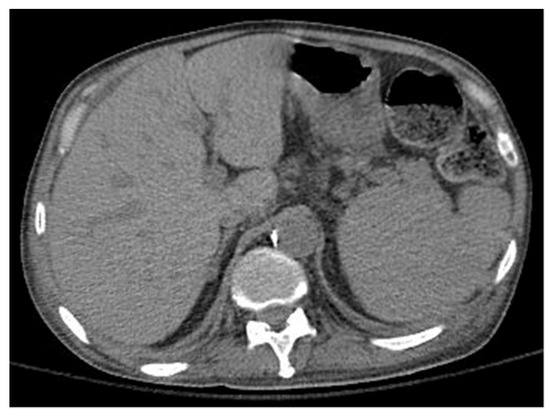

A 63-year-old Caucasian man with an untreated lung disease presented with generalized fatigue and not feeling well. His initial labs revealed cytopenias [Hgb: 10.2 g/dL, WBC: 8.9 K/CUMM, and platelets: 37 K/uL] which on initial evaluation showed dysplastic myeloid lineage cells in the peripheral blood. Failing to follow further workup, he presented to a local emergency room 4 weeks later with leukocytosis [215.5 × 106 per microliter] and pancytopenia [Hgb: 7.1 g/dL, ANC: 4300/uL, and Platelets: 8 K/uL]. He had circulating blasts [65% blasts], and bone marrow examination revealed AML with MDS-related changes and deletion 7 [20/20 metaphases] on karyotyping, and next-generation sequencing identified an FLT3-TKD mutation. The patient’s blast crisis was treated with leukapheresis at an outside facility before being induced with 7 + 3 chemotherapy. The course was complicated by worsening respiratory failure requiring intubation and mechanical ventilation. Chest imaging revealed pulmonary infiltrates (Figure 2a,b), which were not resolving, and the patient had persistent supplemental oxygen requirements even after several days since extubation. He had unusually prolonged pancytopenia, and a D + 28 bone marrow biopsy revealed bone marrow hypoplasia with decreased trilineage hematopoiesis but no evidence of blasts on flow cytometry. However, he was noted to have one metaphase positive for del (7q). He was treated with antibiotics, antivirals, and appropriate mold prophylaxis and then transferred to our facility on D + 34 for lack of bone marrow recovery. D + 38 bone marrow examination revealed similar findings to the earlier biopsy but no del (7q) evidence. Table 1 demonstrates the patient’s lab values showing cytopenia despite treatment indicating the patient’s progressing bone marrow failure.

Further probing revealed that the patient’s history of pulmonary disorder was never treated nor investigated. Physical examination revealed abnormal skin hypopigmentation and oral leukoplakia. The patient’s radiographic studies showed scoliosis with advanced degenerative spondylosis and steatosis of the liver with diffuse hepatocellular changes despite having no history of alcoholism (Figure 3). Of note, family history was significant for the patient’s mother and sister dying of rapidly progressing fulminant PF in their 50 s.

Figure 2. (a,b) Computerized tomography of the thorax demonstrating patient’s irregular pulmonary infiltrates, with peripheral cystic changes (honeycombing) and traction bronchiectasis.